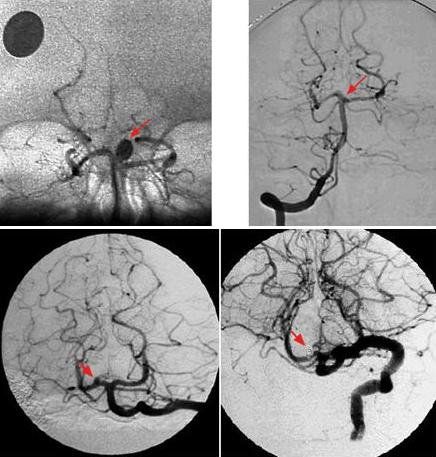

Phác đồ điều trị xuất huyết dưới nhện

Xuất huyết dưới nhện là tình trạng vô cùng nghiêm trọng, có thể ảnh hưởng đến màng não, tủy sống và tính mạng người bệnh nếu không chữa trị kịp thời. Hiện nay để điều trị xuất huyết dưới nhện có nhiều phương pháp, nghiêm trọng nhất sẽ chỉ định phẫu thuật.